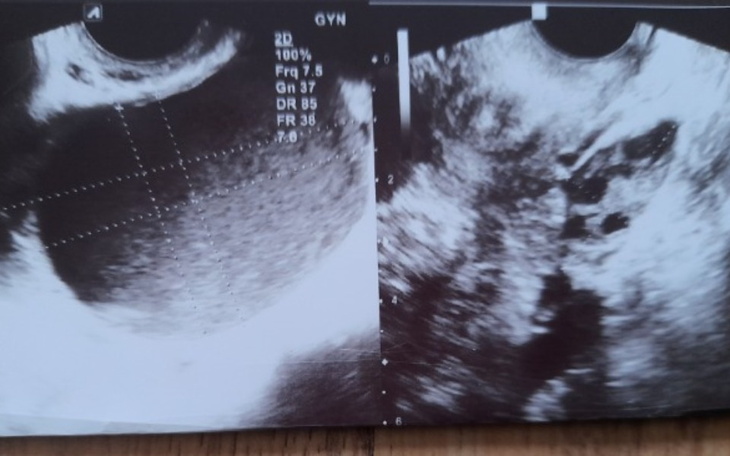

Jestem Karolina, mam 24 lata. Na endometriozę choruję od 2020 roku, dowiedziałam się o tym przez rutynowe badanie u ginekologa, wykazało że mam torbiel endometrialną jajnika 5cm.

Poddałam się operacji, badanie histopatologiczne wykazało łagodną torbiel endometrialną .

Zaszłam w ciążę, ucieszyłam się że trochę mi się wyciszy, że nie będzie się powiększać. I tak też było urodziłam w 2021 roku. Po niespełna 3 miesiącach od porodu, trafiłam z ostrym bólem brzucha do szpitala. Okazało się, że torbiel na jajniku pękł i muszą operować. Po operacji dowiedziałam się, że endometroza się rozszalała. Miałam zrosty jajników, jelita niestety nie dali rady wszystkiego usunąć. Od tego momentu żyję w ciągłym bólu, nie potrafię cieszyć się z macierzyństwa. Próbowałam szukać lekarzy na nfz którzy podejmą się operacji, ale każdy rozkładał ręce i mówił że jedynym wyjściem jest usunięcie wszystkiego wraz z macicą i jajnikami.